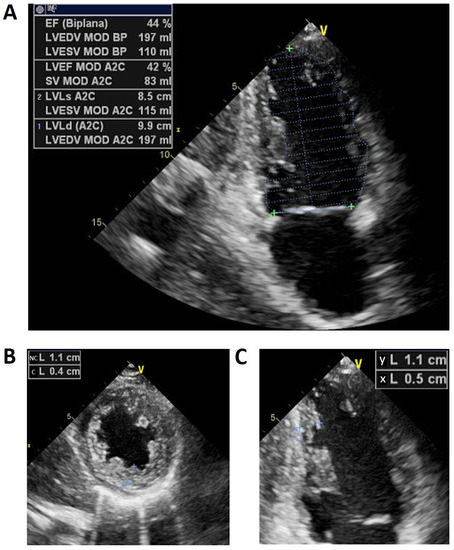

2. Case Presentation